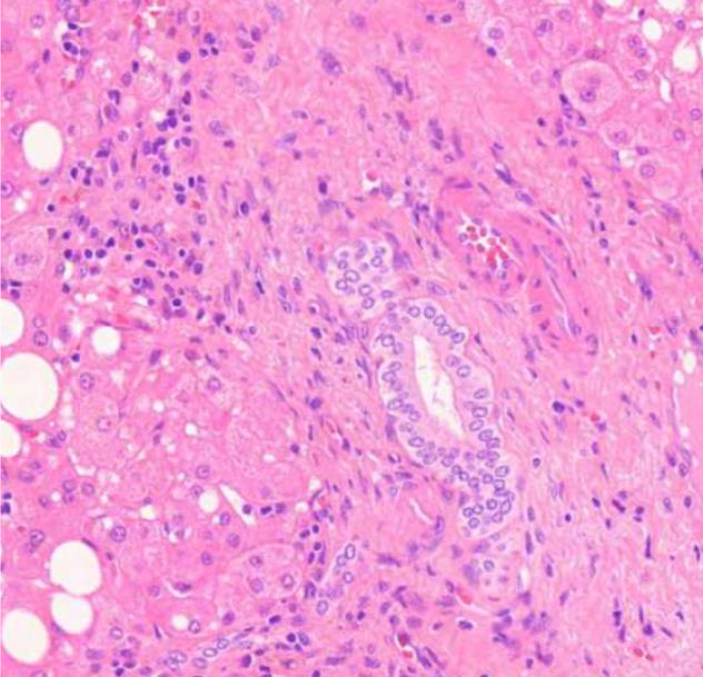

sidekudosseptoja, joiden välissä nodulaarista regeneraatiota

mitä kuvassa näkyy yleisesti ja millainen regeneraatio? (vinkki: maksaskirroosi)

hydrooppista hepatosyyttien degeneraatiota

millaista degeneraatiota kuvassa näkyy? (vinkki: maksaskirroosi)

sappistaasia

mitä on hepatosyyttien välissä? (vinkki: maksaskirroosi)

maksaskirroosi

sappitieproliferaatiota ja lievää lymfosyyttilisää